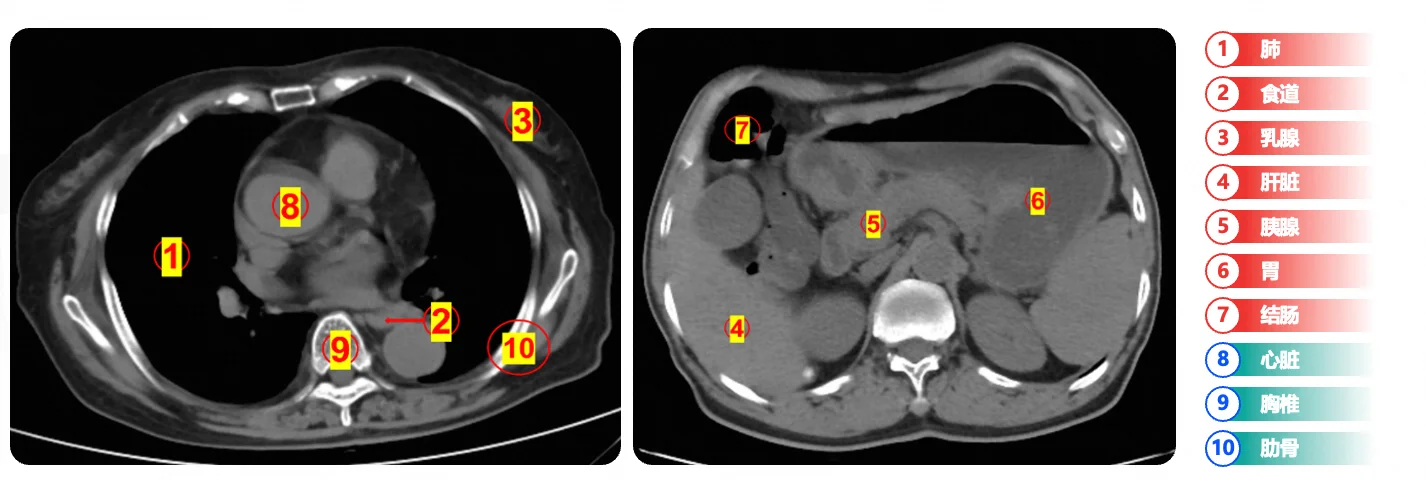

效率和价值的革新:阿里达摩院的“平扫CT+AI”技术,能在一次平扫CT中,快速识别胰腺癌、胃癌等多种癌症和急重症。